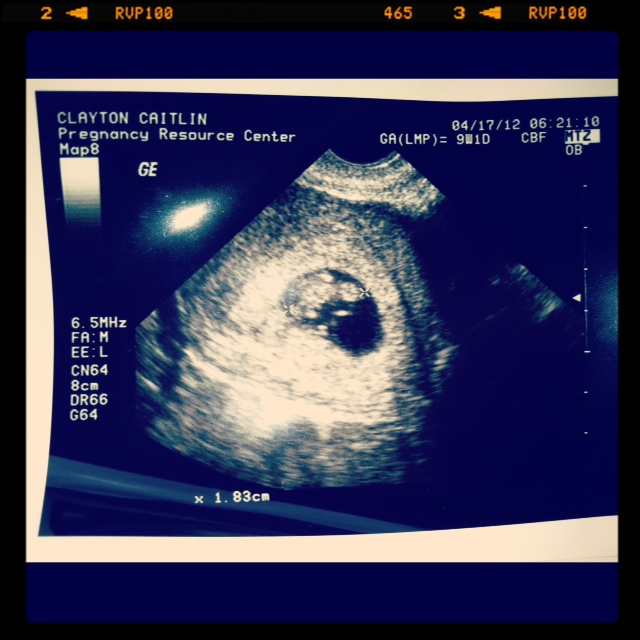

This is supposed to be 12 weeks, but we haven't been to a doctor yet so this its just an estimate as of 4.17.12.  Today, I should be about 17 weeks.  We just got back from the hospital for blood/urine tests(FUN!) and we have our first real baby appointment on Monday morning!!!  So excited!  We will for sure hear his/her heartbeat for the first time, find out a more exact time period, and MAYBE even find out the gender.  Ahhhhh!!!